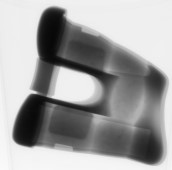

Трехмерное сканирование искусственного сустава

В 2018-2019 годах наша компания выполнила задание по индустриальному компьютерному томографическому исследованию искусственных суставов для определенной медицинской компании. CT-сканирование создает двухмерные плотностные изображения поперечных срезов внутри искусственного сустава, которые могут быть использованы для создания трехмерной модели объема искусственного сустава из множества снимков с различных ракурсов, а затем эти изображения могут быть восстановлены на компьютере. В виде двухмерных срезов или трехмерных объемных изображений это является наилучшей техникой бесконтактного контроля и оценки, позволяющей четко, точно и наглядно показать внутреннюю структуру, состав, материал и дефекты искусственного сустава. Индустриальное компьютерное томографическое исследование широко применяется в автомобильной, материальной, железнодорожной, космической, авиационной и других отраслях промышленности, предоставляя важные технические средства для анализа геологической структуры, повышения безопасности железнодорожного транспорта при увеличении скорости и грузоподъемности, прогнозирования запасов нефти, а также для оценки качества механических изделий и т. д.